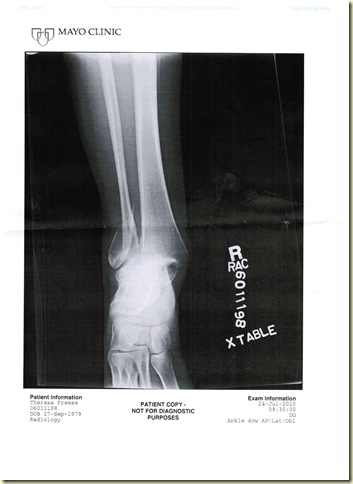

Well, I am finally boot and cast free! Yippee!!!!! I thought I would share some pictures of my before and after x-ray's, primarily for my friend Martin, but maybe there are others that are interested too. Enjoy!!!!!!